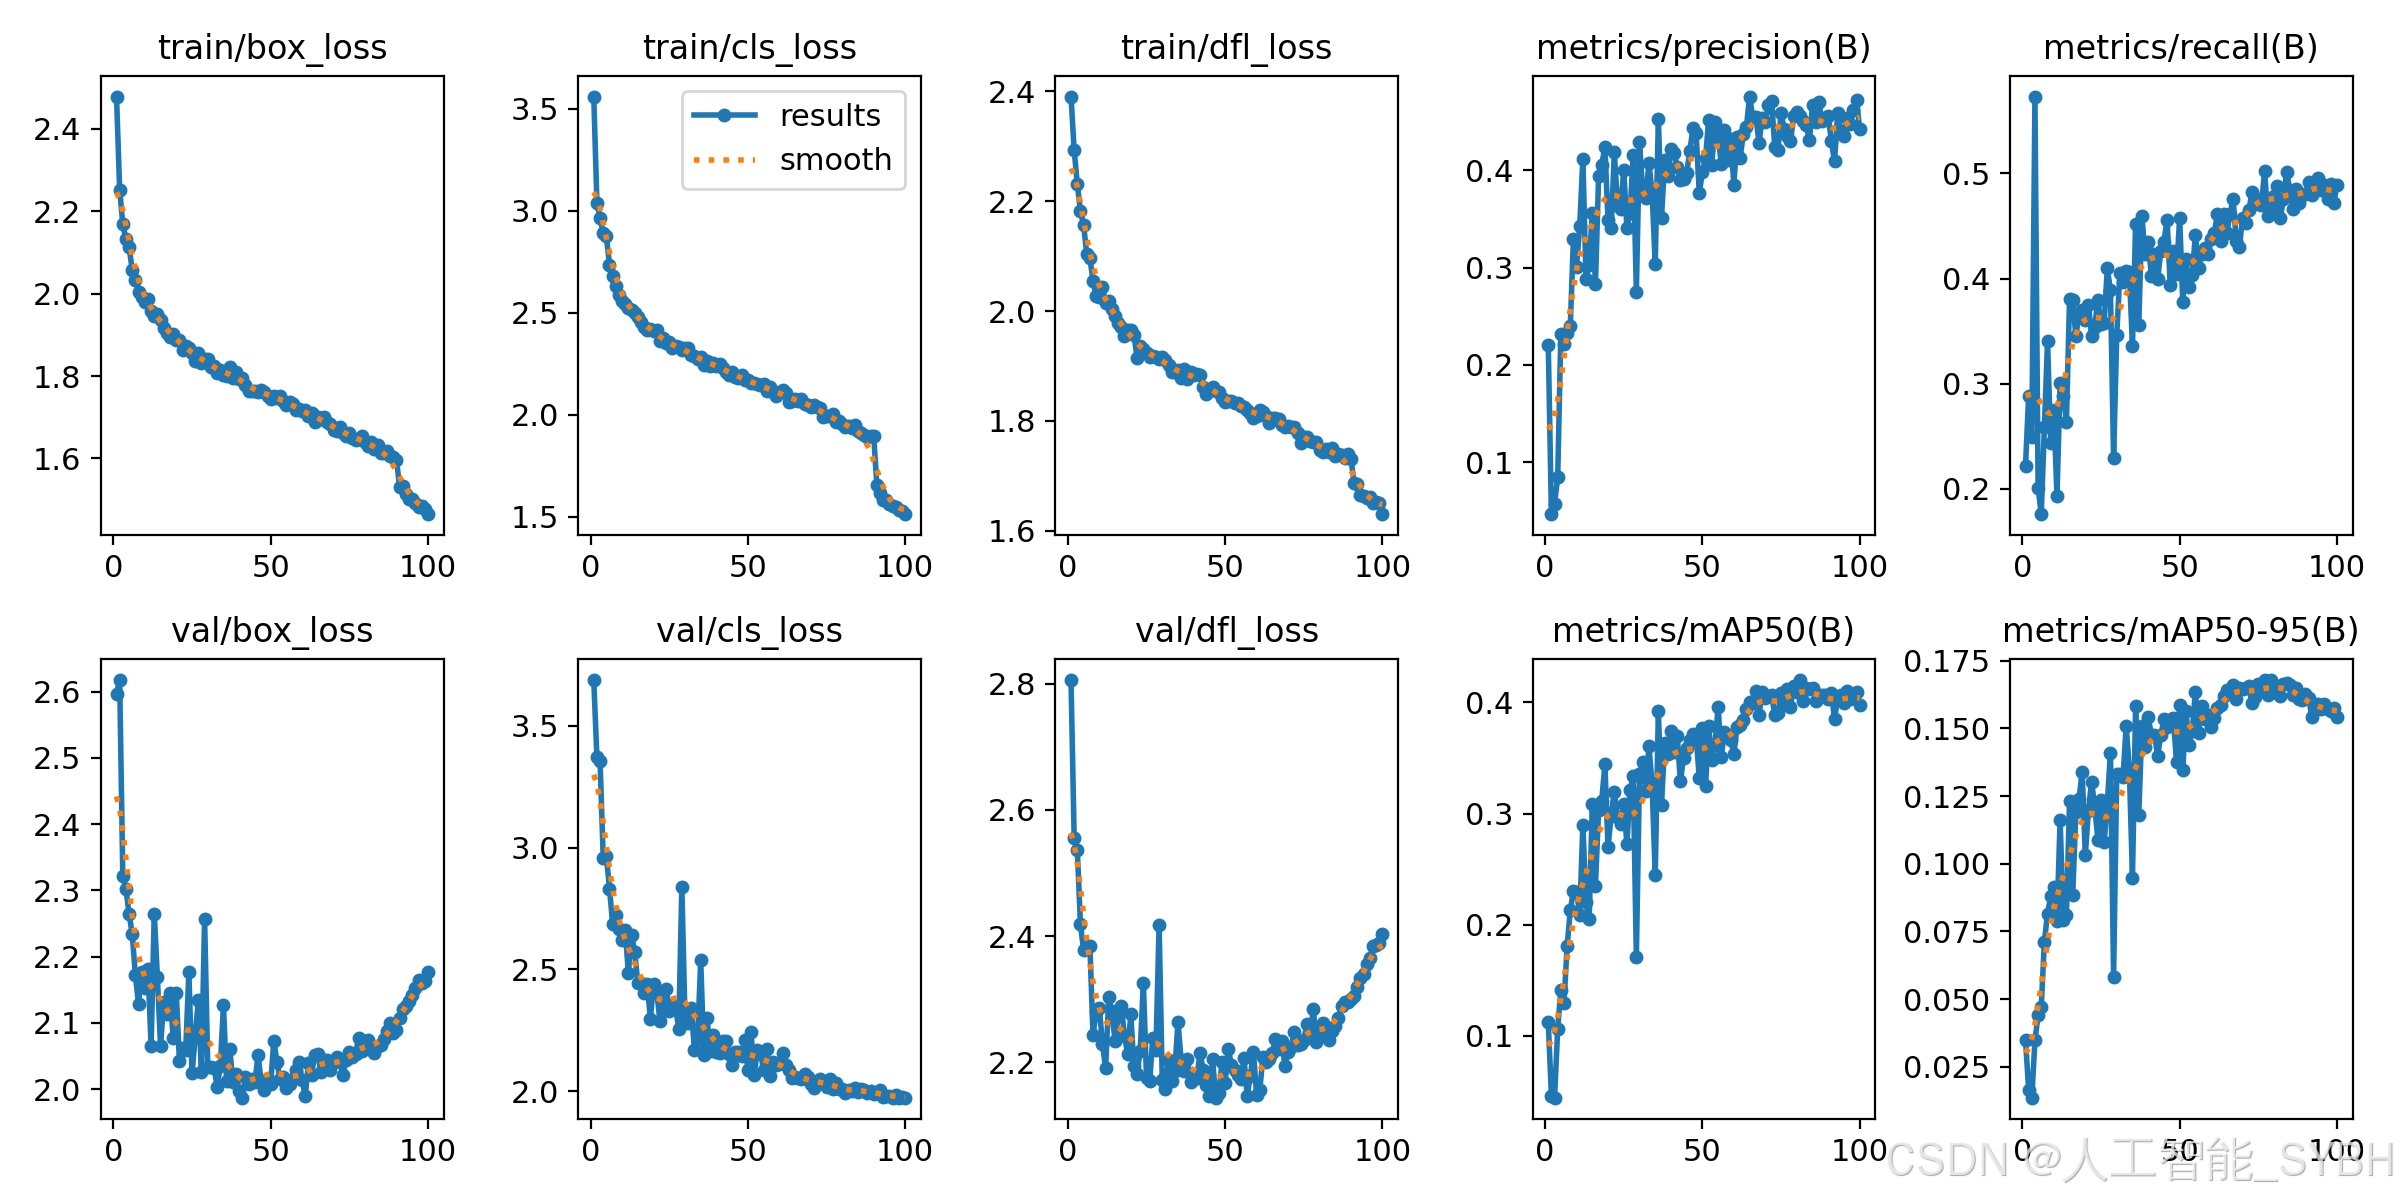

训练结果